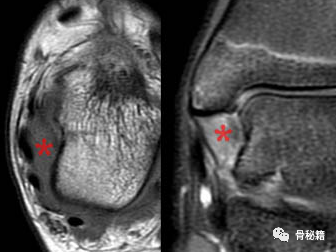

15 岁女性,急性内翻外踝扭伤。轴向 T1 加权(左)和冠状脂肪抑制(右)图像显示 PTTL 的正常条纹丢失,信号增加表明水肿和挫伤(星号)。